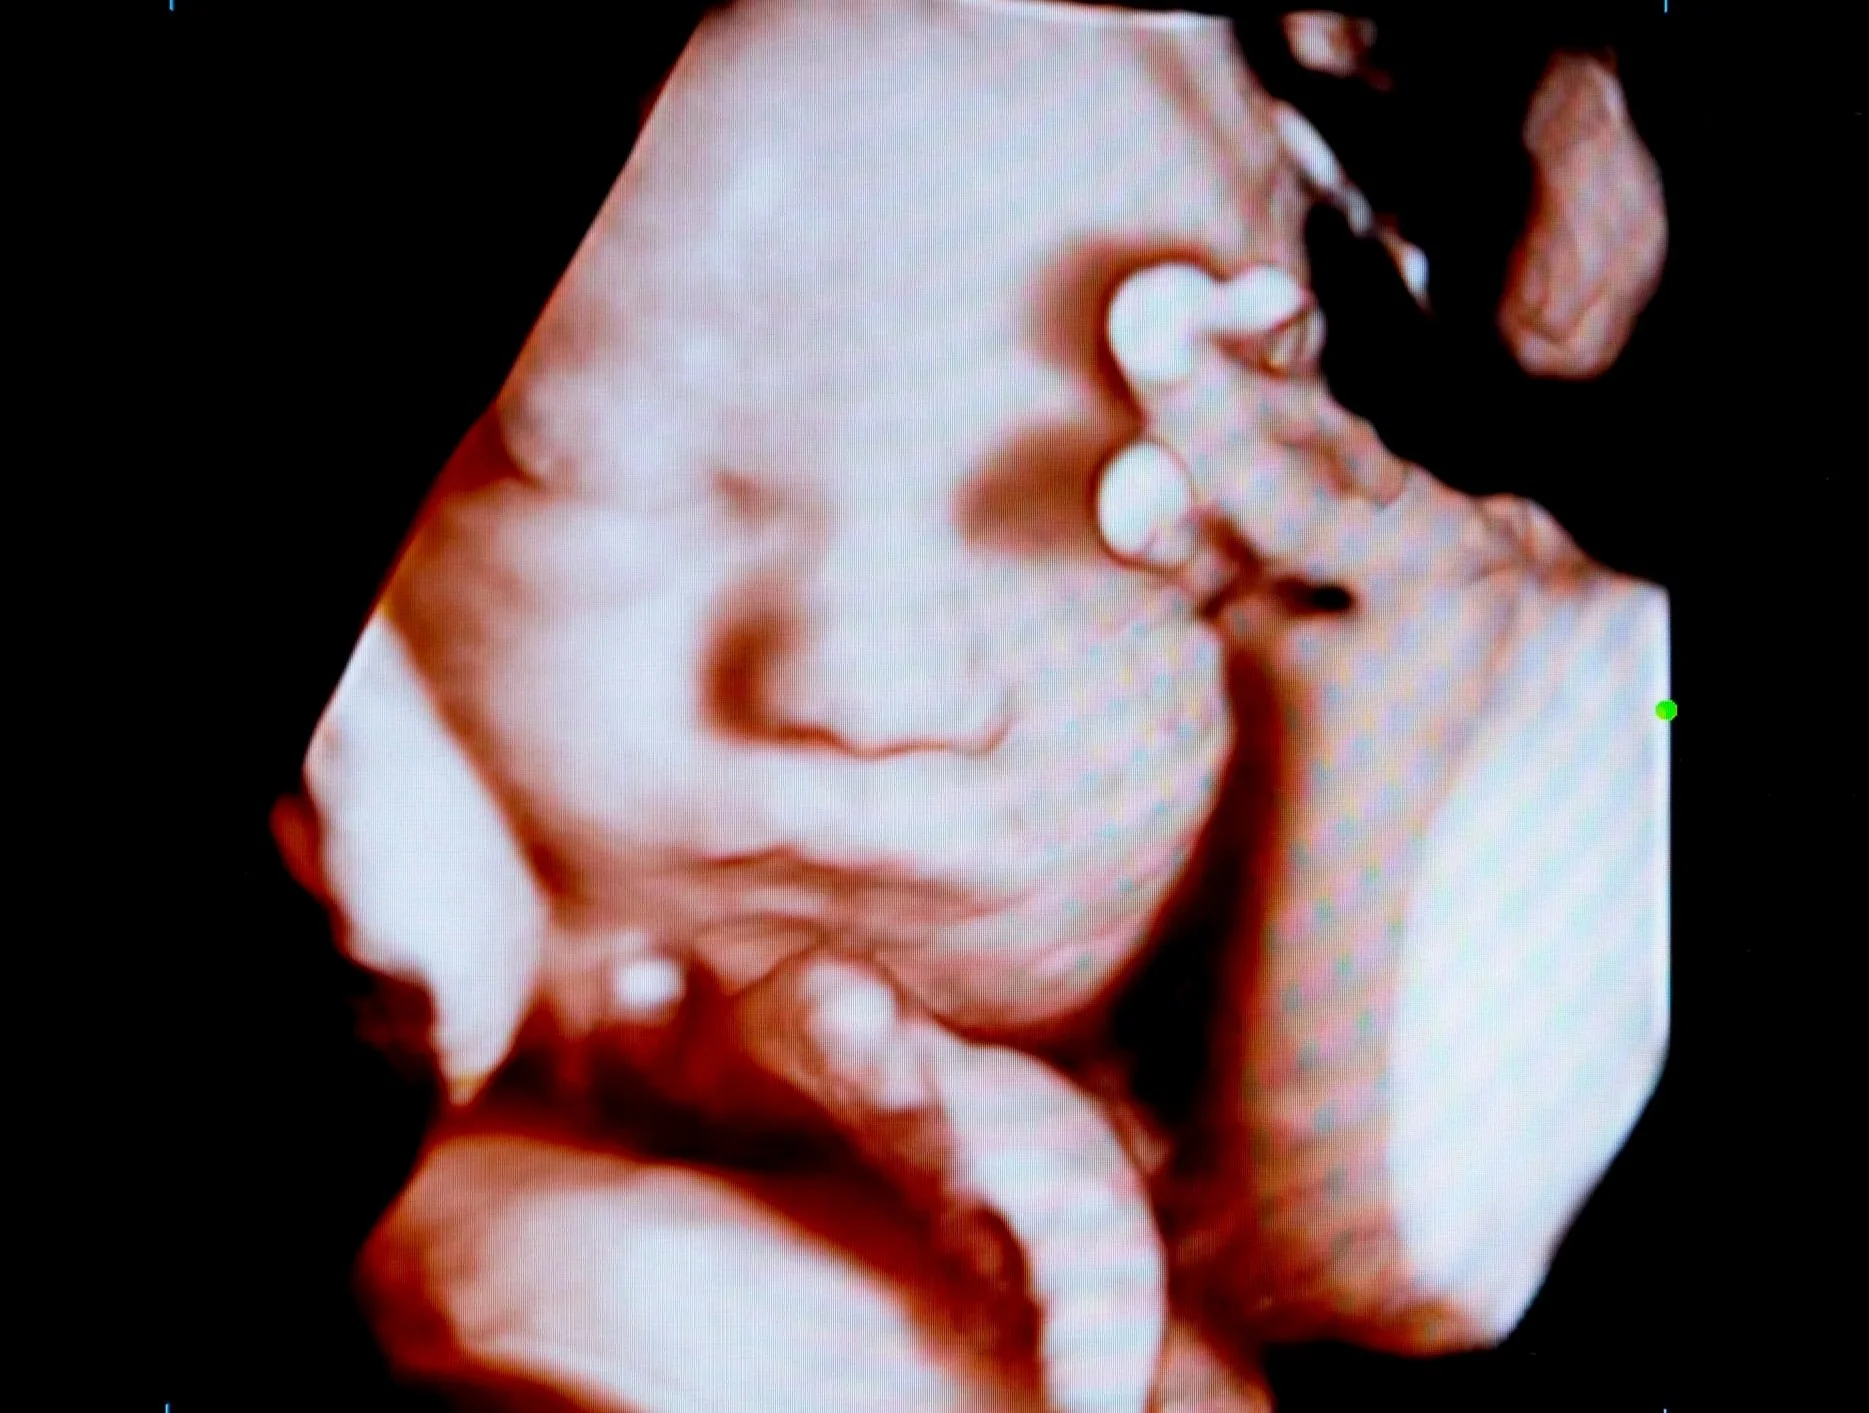

Pretecho

Een echo die niet medisch noodzakelijk is, noemen we een pretecho, bijvoorbeeld een echo voor geslachtsbepaling of een 3D/4D-echo. Deze echo’s laat je op eigen initiatief maken en ze worden niet vergoed door de zorgverzekeraar. Wij maken geen pretecho’s in de praktijk, maar verwijzen je hiervoor graag naar een gespecialiseerd echocentrum.